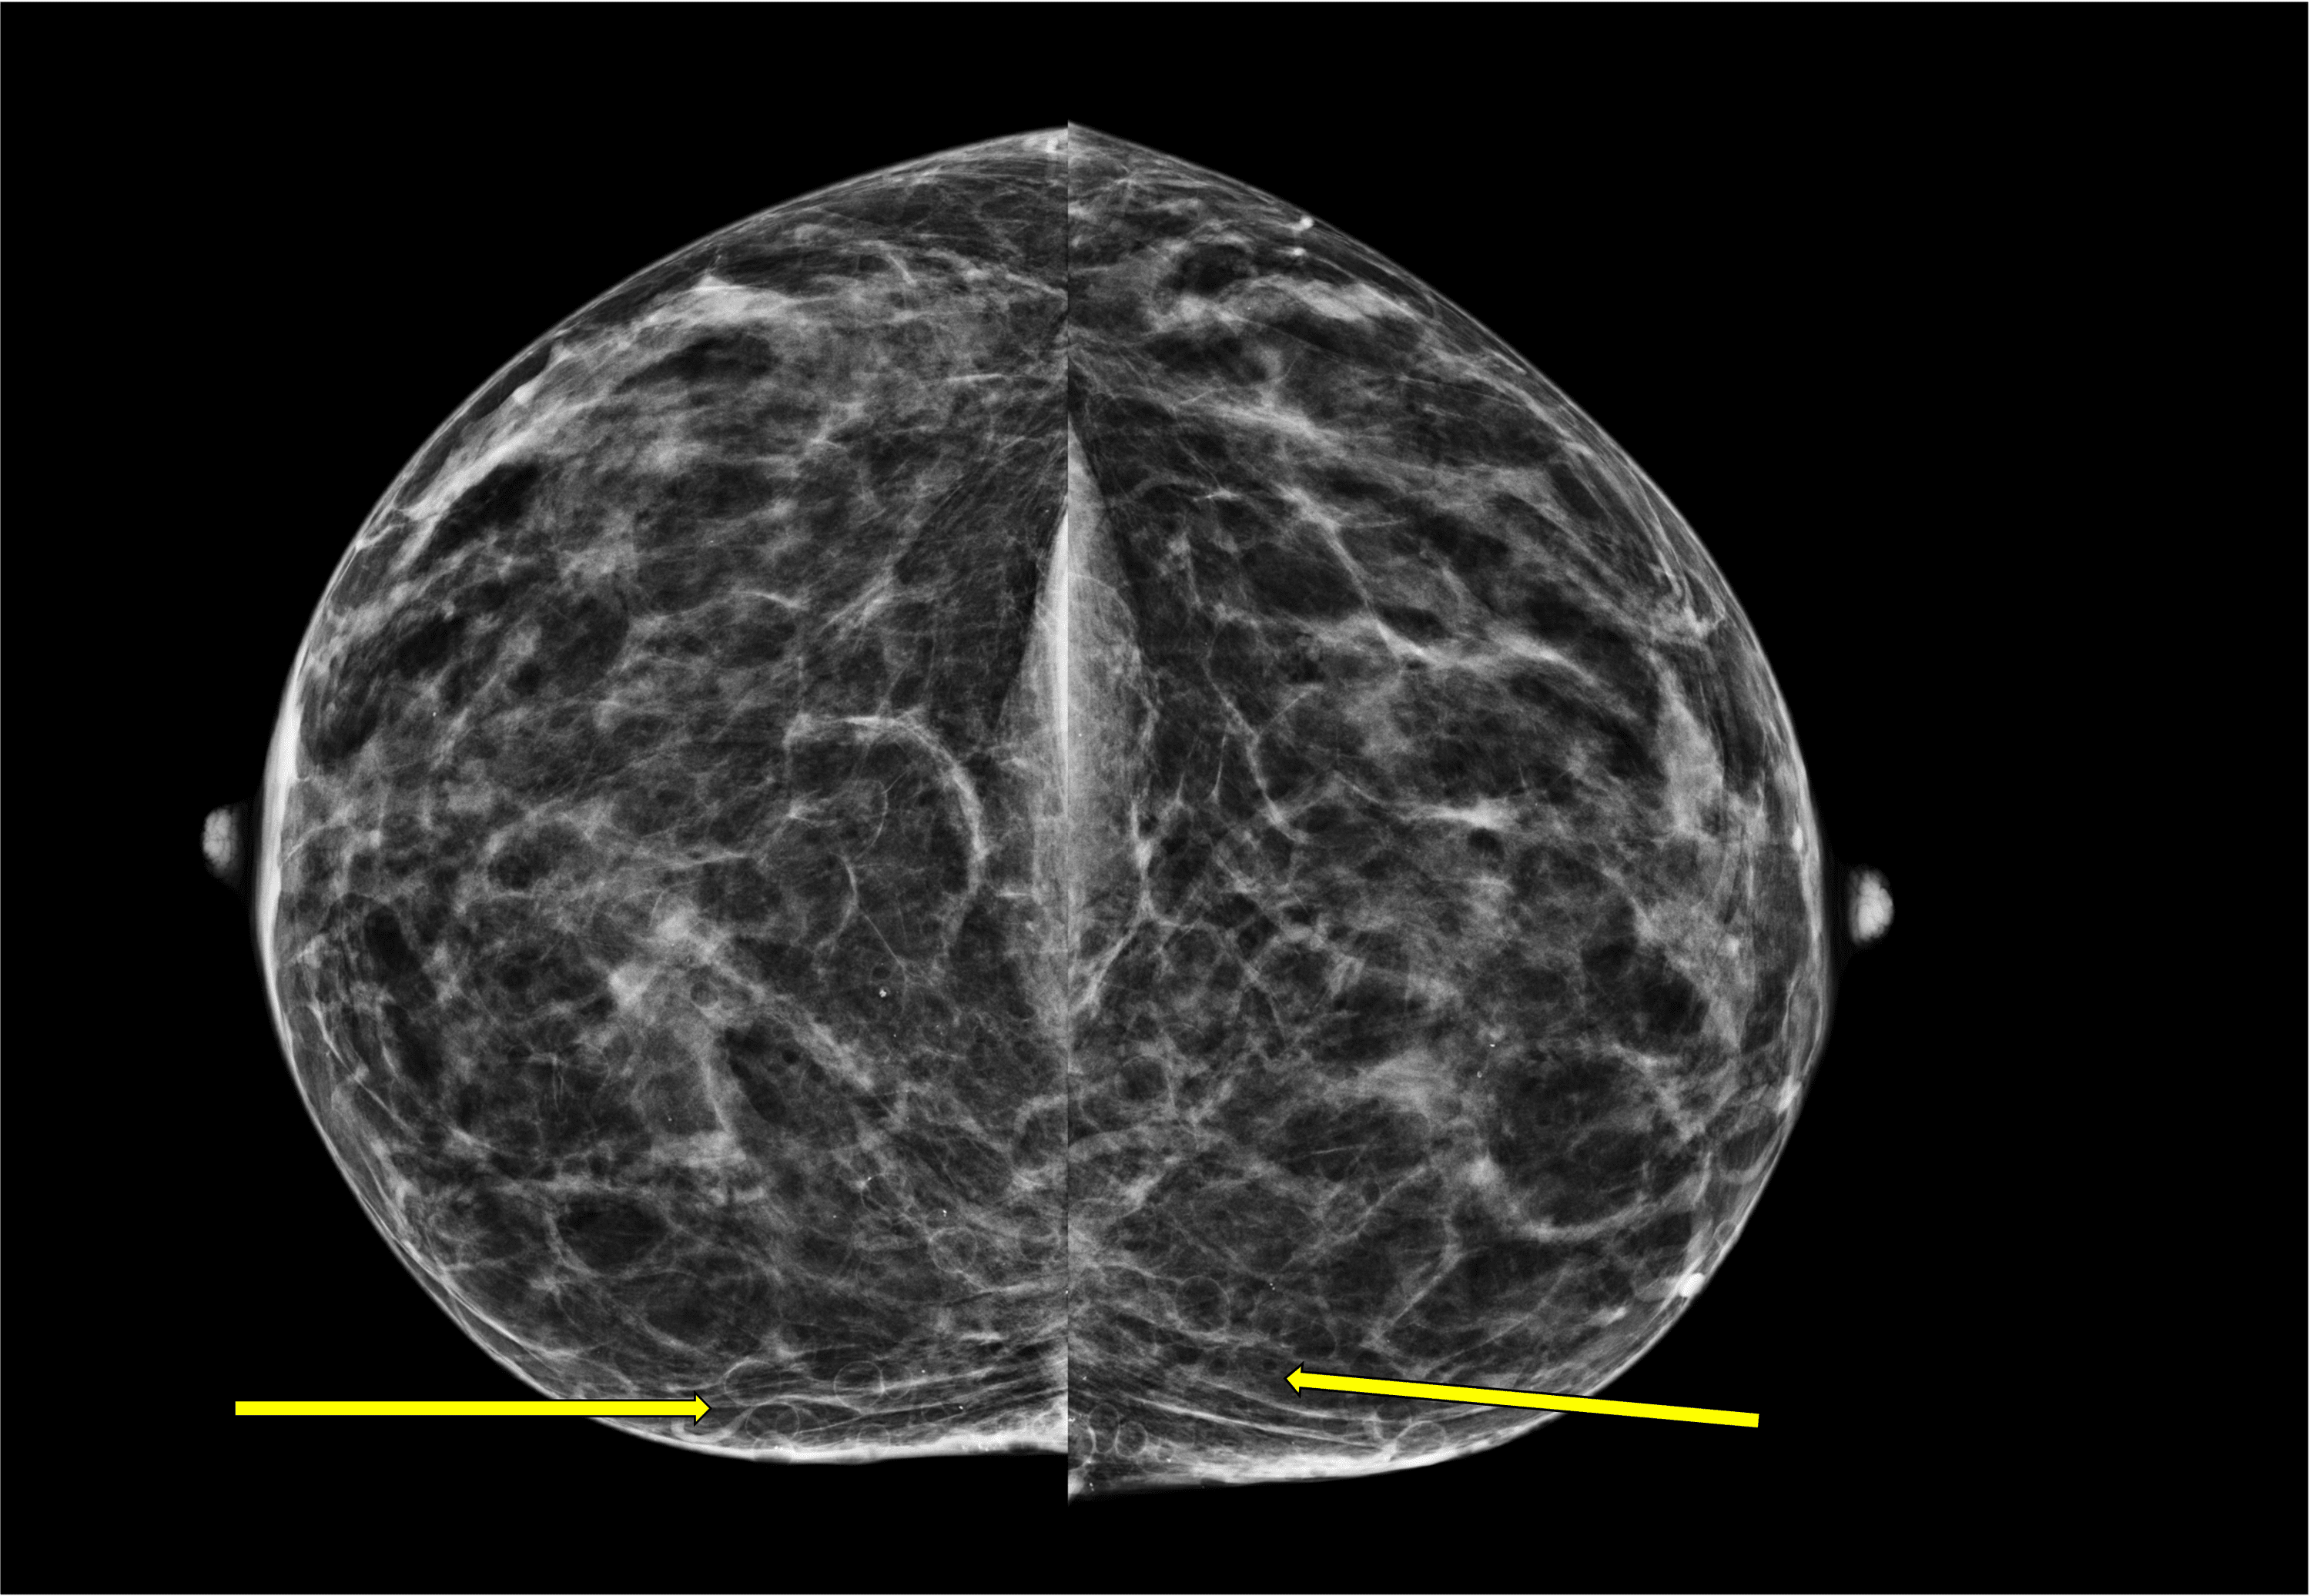

Mammographic architectural distortion caused by cyst aspiration Noel Miner, Meng, 2019

From journals.sagepub.com

Mammographic architectural distortion caused by cyst aspiration Noel Miner, Meng, 2019 Painful Breast Cyst Mumsnet Hello, im 44 and had the same thing, lump on my bra line that is more on my rib cage but the top part is attached to the skin of my breast. I think i'm probably what's called oestrogen dominant and that leads to these cysts. I've definitely had a drop off of oestrogen lately. 2 months ago one of. Painful Breast Cyst Mumsnet.